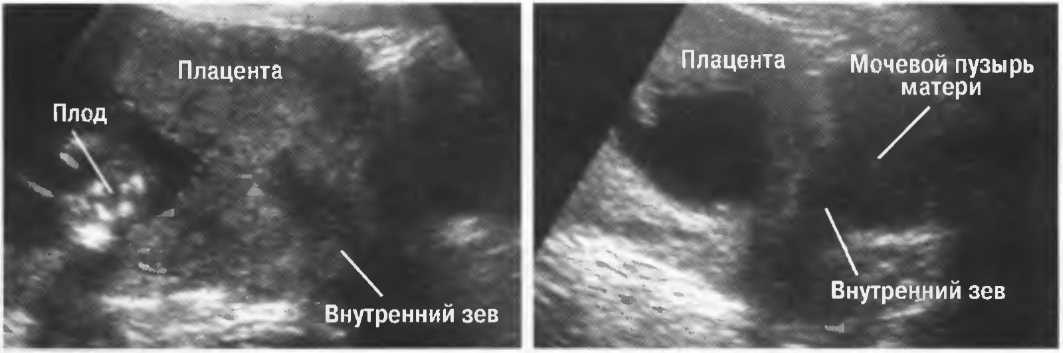

Подготовка

1. Подготовка